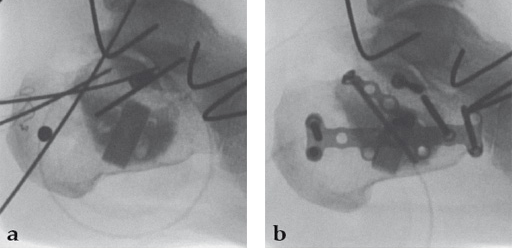

Case 1: A 70-year-old man sustained a Sanders IIA fracture of his left calcaneus.

(Case provided by Michiel Verhofstad, Tilburg, The Netherlands)

After open reduction a gap was left due to impaction of the osteoporotic metaphyseal bone. To support preliminary maintenance of the primary reduction a block of calcium phosphate was introduced beneath the posterior facet. The rest of the gap was filled with Norian drillable. After hardening plate osteosynthesis was performed. Two screws were placed through the fiber-enhanced calcium phosphate. Weight bearing was started 6 weeks later. After 6 months the fracture was healed without secondary loss of reduction. Note that at that time the degradation of the void filler is visible.